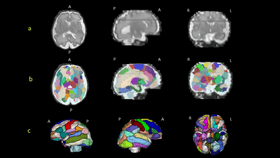

A new study, being presented at this year’s American Association for Anatomy annual meeting, during the Experimental Biology 2022 meeting, has found significant differences in brain structures of people with autism compared to those without. But even more amazing is that these differences were noticeable as early as 25 weeks gestation – or to put it another way: more than three months before birth. The discovery offers potential for earlier diagnosis for people with autism.

“To the best of our knowledge, this is the first attempt to semi-automatically segment the brain regions in the prenatal stage in patients who are diagnosed with autism later and compare different groups of controls,” Ortug said.

But if it’s partially genetic, the team reasoned, then perhaps they could find signs of the condition turning up during fetal development. They analyzed 39 MRI scans taken of living fetuses at around 25 weeks gestation – the scans had already been taken regardless of the study, not specifically for it – to see if they could spot any differences in brain structure between children who would go on to develop autism and children who wouldn't.

Their hunch paid off: the scans of fetuses that went on to receive an ASD diagnosis showed significant differences in an area of the brain known as the insular lobe. That’s a region responsible for things like self-awareness (both physical and emotional), social abilities, and behavior regulation – all things people with ASD can have real trouble with.

“Our results suggest that an increased volume of the insular lobe may be a strong prenatal MRI biomarker that could predict the emergence of ASD later in life,” explained Ortug.

Scans from children with ASD also showed an enlarged amygdala and hippocampal commissure.